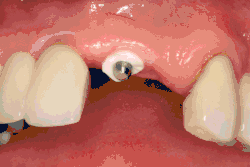

The area of the mouth that is missing a tooth is identified.

An area with a single missing tooth